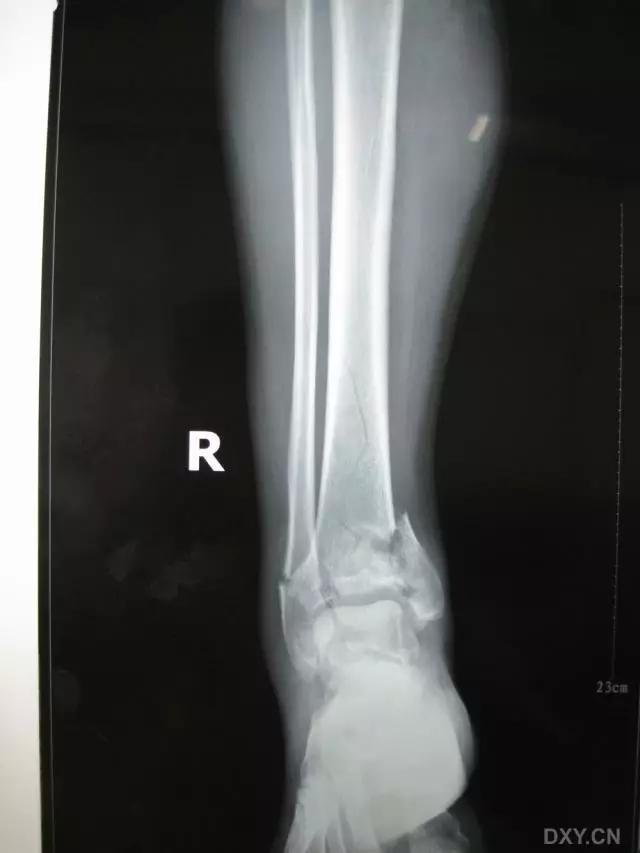

6. Pilon 骨折

涉及负重关节面(胫距关节面)与胫骨远侧干骺端的骨折。其典型特征是干骺端存在不同程度的压缩、干骺端的压缩粉碎性骨折不稳定、原发性关节软骨损伤以及永久性关节面不平整导致预后不良。

pilon 骨折正位片

pilon 骨折侧位片

pilon 骨折三维 CT 表现